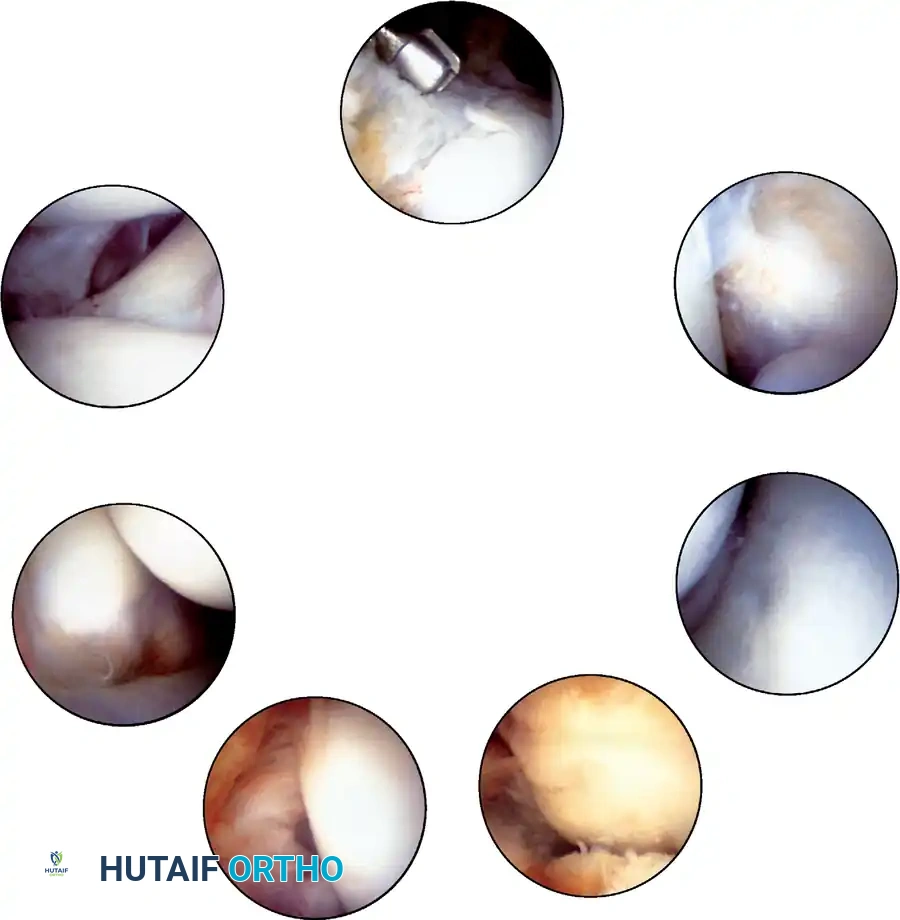

Initial arthroscopic view upon entering the anterior compartment, demonstrating the tight congruency of the tibiotalar joint.

4. The Systematic Diagnostic Tour

Any arthroscopic procedure must begin with a thorough, reproducible, systematic examination of the joint to ensure no concomitant pathology is overlooked. The ankle is conceptually divided into anterior and posterior compartments, each further subdivided into medial, central, and lateral zones.

The Anterior Compartment Sweep:

* Anteromedial Zone: Visualize the deep portion of the deltoid ligament, the medial talomalleolar articulation, and the medial tibiotalar joint. Look for medial gutter synovitis or osteophytes.

* Central Zone: Sweep across the dome of the talus and the corresponding tibial plafond. Probe the cartilage for softening, fibrillation, or frank osteochondral defects. Dynamic plantarflexion and dorsiflexion under traction significantly improve exposure of the talar dome.

* Anterolateral Zone: Examine the lateral tibial plafond, the lateral talomalleolar articulation, and the intra-articular portion of the anterior talofibular ligament (ATFL).

* Anterior Gutter: Sweep the scope distally over the talar neck. Inspect the anterior lip of the tibia for impingement osteophytes (often seen in athletes) and thoroughly check the anterior gutter for hidden loose bodies.

Arthroscopic view of the anterolateral gutter demonstrating synovial hypertrophy and soft-tissue impingement.

Arthroscopic visualization of an osteochondral defect (OCD) on the medial talar dome.

The Posterior Compartment Sweep:

In ankles with adequate ligamentous laxity or sufficient non-invasive distraction, the posterior compartment can be viewed from the anterior portals.

* Evaluate the posteromedial, central, and lateral tibiotalar articulations.

* Inspect the posteroinferior tibiofibular ligament and the transverse ligament.

* Loose Body Hunt: Loose bodies frequently migrate and become entrapped posterior to the tibiofibular ligaments. The surgeon should manually massage the posterior soft tissues of the ankle to express potential loose bodies into the arthroscopic field of view.

Arthroscopic view of the posterior gutter, a common hiding place for intra-articular loose bodies.

Further visualization of the posterior compartment structures, including the transverse ligament.